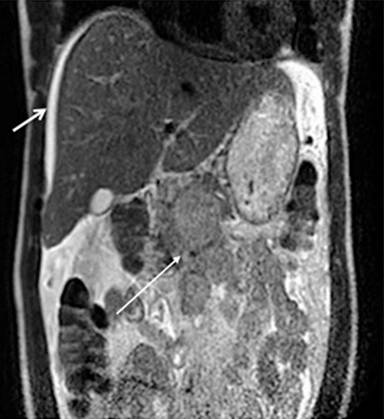

Patient #1

A 32-year-old African man was admitted for right upper quadrant abdominal pain. Two weeks earlier he presented with fever, night sweats and coughing. His last trip to Africa was 8 years earlier. Chest CT scan showed bilateral pleural effusion with normal mediastinal lymph nodes. Abdominal ultrasound showed perihepatic ascites, enlarged lymph nodes within liver hilum and a solid pancreatic mass. Abdominal CT san and magnetic resonance imaging (MRI) showed a heterogeneous solid mass located in and adjacent to the pancreas (Figure 1). EUS confirmed a heterogeneous mass adjacent and involving pancreatic parenchyma at the genu. FNA revealed granulomatous necrotic lesions compatible with tuberculosis. The patient was put on quadritherapy (rifampicin, isoniazid, ethambutol and pyrazinamide) with a rapid clinical improvement.

|

Figure 1. Abdominal MRI: ascites (short arrow) and a heterogenous solid mass located in and adjacent to the pancreas (long arrow) (Patient #1). |